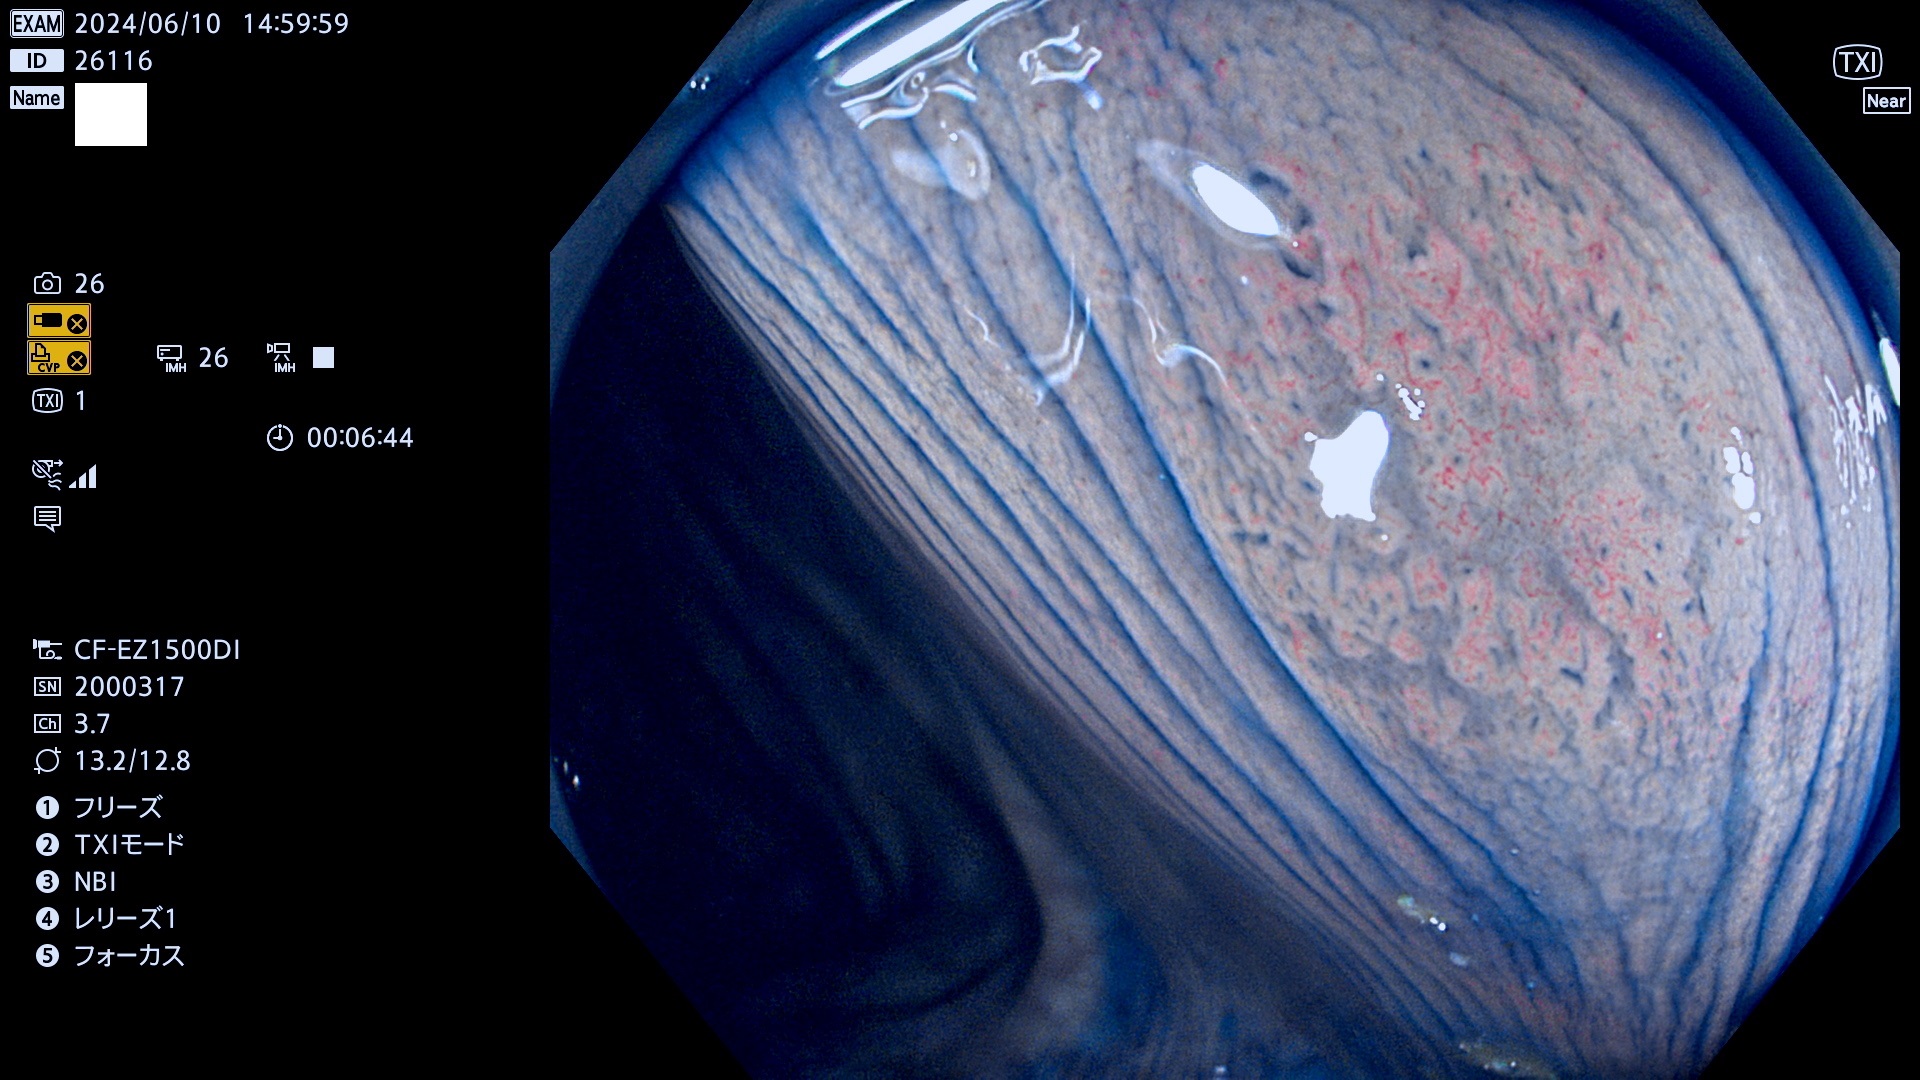

今週のUb、Uc型腺腫

表面型腺腫(Flat Adenoma)の中で、完全に平坦な物をUb、陥凹している物をUcと呼びます。平坦隆起型(Ua)よりも、発見が難しく危険な病変です。

毎週の検査(木・金・土・日)に発見されたUb、Uc型・腺腫を、その週の日曜の夜にUPし1週間、提示します。

抽出の対象期間 2024年6月6日〜6月10の5日間(50件の検査)7件 (7/50=14%)